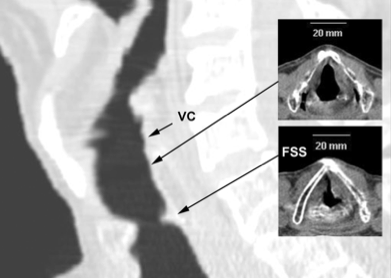

- Se realizó una fibrobroncoscopio que evidencio un estenosis subglótica del 75 % y se realizo un CT que mostraba una anillo a 1,2 cm de cuerdas vocales.

- Las causas de estenosis subglótica pueden ser congenitas (1/10.000 nacimientos), como secuelas de una difteria, o yatrogénicas tras intubaciones prolongadas. La disnea es más comun que el estridor, la ronquera, la tos o la cianosis. En adultos las estenosis subglóticas suelen diagnosticarse tras problemas con la intubación.